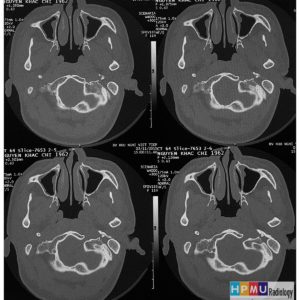

Chấn thương hàm mặt

Lượt xem: 275» 01-11-2018 -

Chấn thương hàm mặt

Lượt xem: 180» 01-11-2018 -